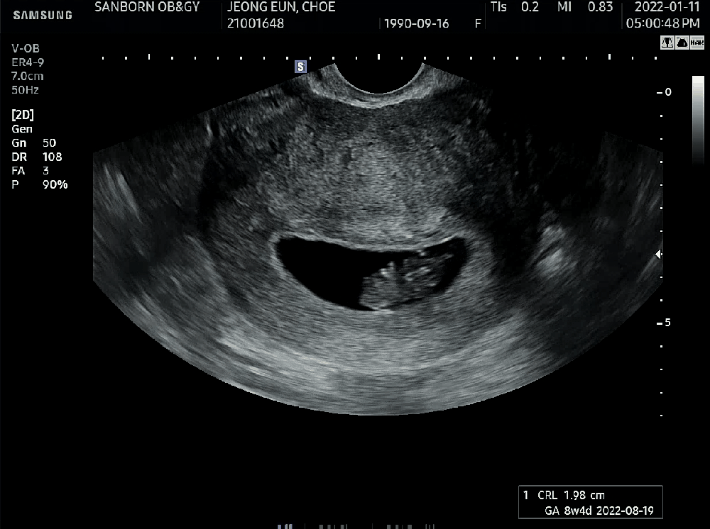

오늘의 호띵이의 키는 아래 초음파 사진과 같단다. (키 : 1.98cm, 심장박동 : 180BPM)

6주차에 호띵이가 0.62cm였는데 2주만에 호띵이가 1.36cm이나 자라고 엄마 뱃속 작은 아기집에서 꾸물거리는 호띵이를보며 신기함과 뭉클함을 느꼈다.

[호띵 엄마의 초음파 사진첩]

호띵엄마는 초음파 사진첩에 호띵이 초음파 사진 주차별로 차곡차곡 정리중이란다.

호띵엄마도 호띵이 많이 기다리고 있음을 호띵이가 알아주길 바라는 마음에서 참조하라고 사진을 첨부하였다.